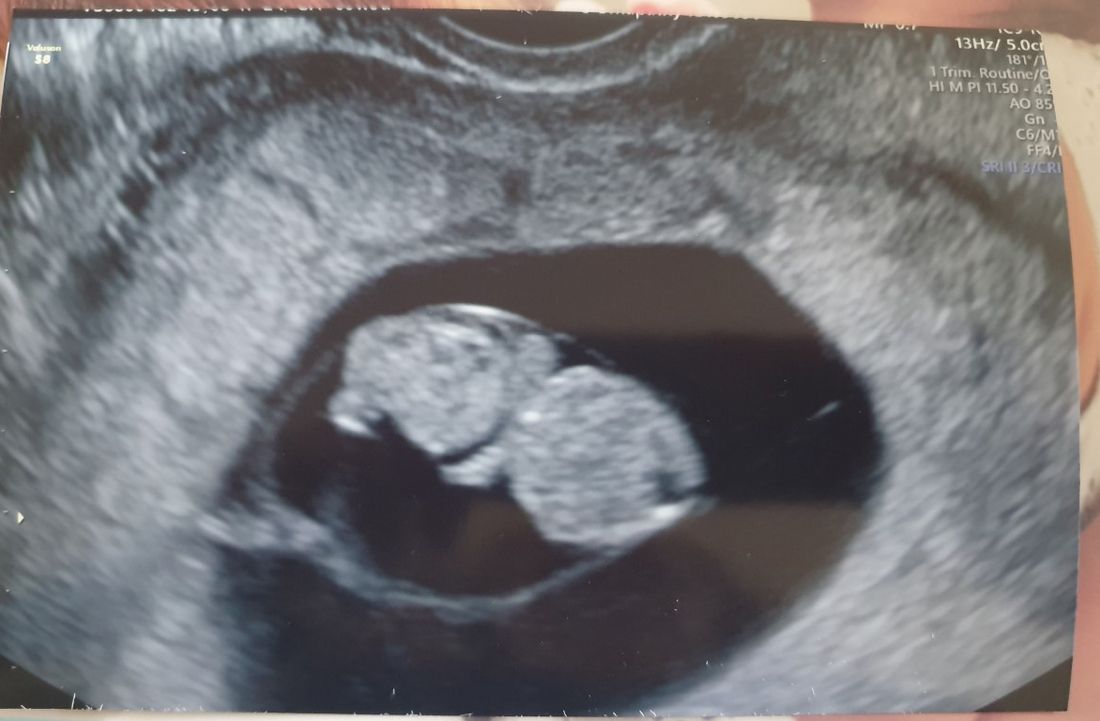

But, just four days after accepting her fiancé Ed Painter's proposal, she discovered she was pregnant again. And, this time, thanks to participating in a medical trial through Tommy's – a charity providing research into miscarriages, premature and stillbirths – she has passed the 24-week milestone when, if a baby is born, the NHS believes it has a chance of surviving.

Despite miscarrying five babies between 2016 and 2019, Danielle refused to be beaten and in September was referred to Tommy's, where experts have worked tirelessly to discover the underlying cause of her difficulties, leading to her being accepted on to a medical trial in June this year.

Then, in June, Danielle saw Tommy's was offering a trial for women to start taking progesterone when they had a positive ovulation test, and she asked to take part.

According to research carried out by the Tommy's National Centre for Miscarriage Research, giving progesterone to pregnant women with early pregnancy bleeding and a history of miscarriage could increase their chances of having a baby.

Doctors agreed and, with a new plan in place, her hopes of having a successful pregnancy were restored.